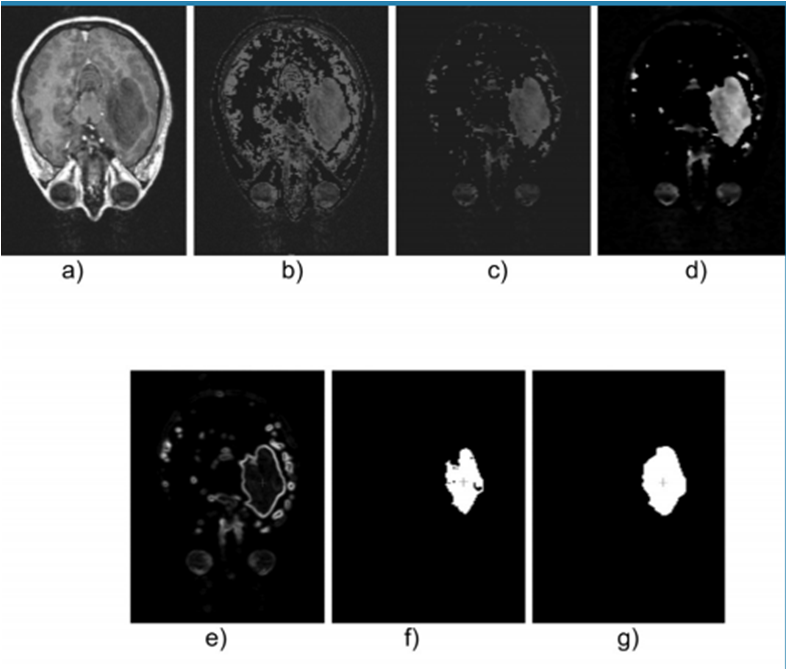

Figure 5, shows a 2-D view of both the original LGG and the processed versions after applying the proposed technique.

The optimal sizes for the Erosion, Median and Dilation filters were (3,3,3), (3,3,3) and (5,5,5), respectively. Regarding the trained LSSVM, values of 1.00 and 1.25 were obtained as optimal parameters for γ and σ2, respectively. These parameters were arrived at by means of the error present when comparing the manual and automatic coordinates, considering the percentage relative error (PrE). For this minimum value of PrE, the optimal values of RG’s parameters, r and m, were 1 and 5, respectively.

The best automatic segmentation of the LGG yielded a volume of 43.5375 cm3; while the volume associated with manual segmentation of the tumor, was 44.1677 cm3. This implies that the minimum PrE was 1.43%.